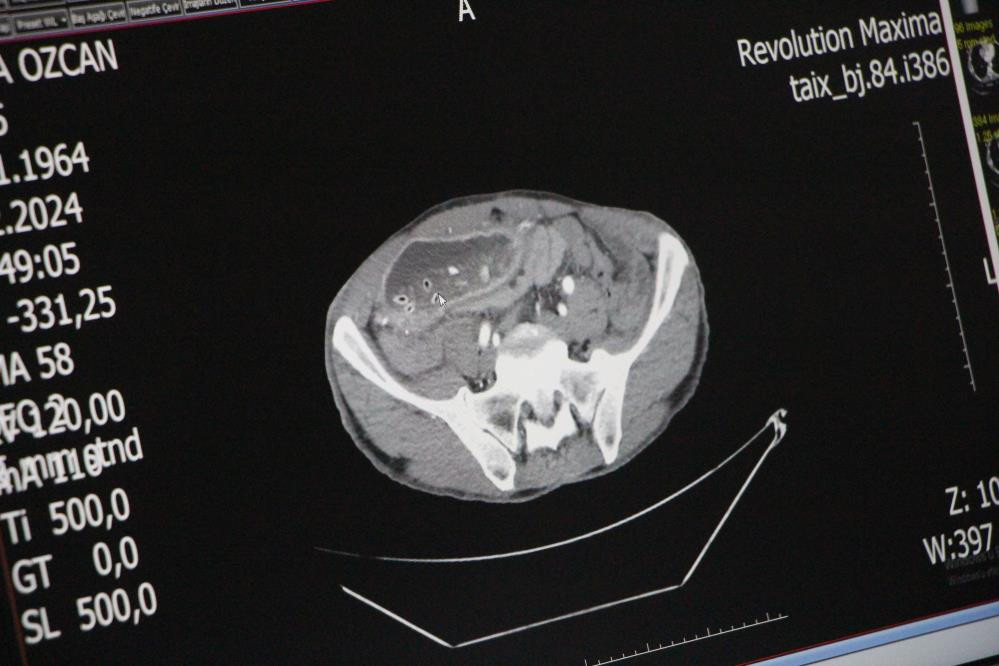

Yapılan endoskopi ve tomografi çekiminin ardından gerçekleşen ameliyatında çıkış kısmı daralan midesinin 10 kattan fazla büyüyerek karın boşluğunu sardığı görüldü. Mide ve karaciğer arasında oluşan doku bandının mideyi ikiye ayırdığını gören Genel Cerrah Doç. Dr. Yavuz Pirhan, ince barsak ile mide arasına yeni bir kanal yaptı.

Yetişkinlerde çok nadir görülen bu durumla genelde yeni doğan bebeklerde karşılaşılması üzerine hemen müdahale edildiğini anlatan Doç. Dr. Pirhan, "20 yıllık genel cerrahi uzmanıyım. Bu benim gördüğüm ikinci vaka. Hastamızın karnının içinin yarısından fazlası mide dokusu şeklindeydi. Hamile bir bayan gibi şişliği vardı. Şimdi karnı dümdüz oldu. Hatta kaburga uçları bile görünüyor" diye konuştu.